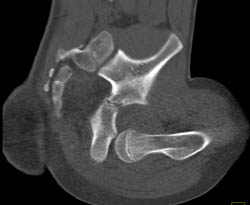

GSW to Axilla With Active Bleed and Hematoma. Nice CTA